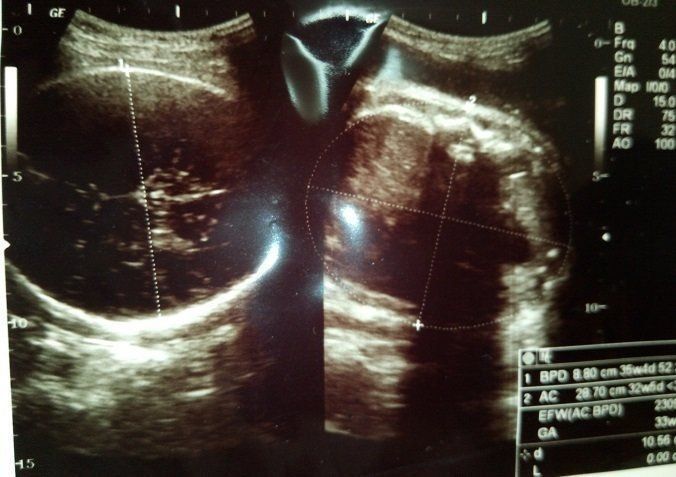

妊娠35週のエコー写真 赤ちゃんの推定体重2309g

この頃もまだ股関節痛がひどく、医師に相談しました。でも、「出産に向けての準備だから仕方がない」の一言に撃沈。やはりストレッチなどをして、うまく乗り切るしか方法がないようです。「生活に支障が出ているというのに」と、思わずにいられませんでした。